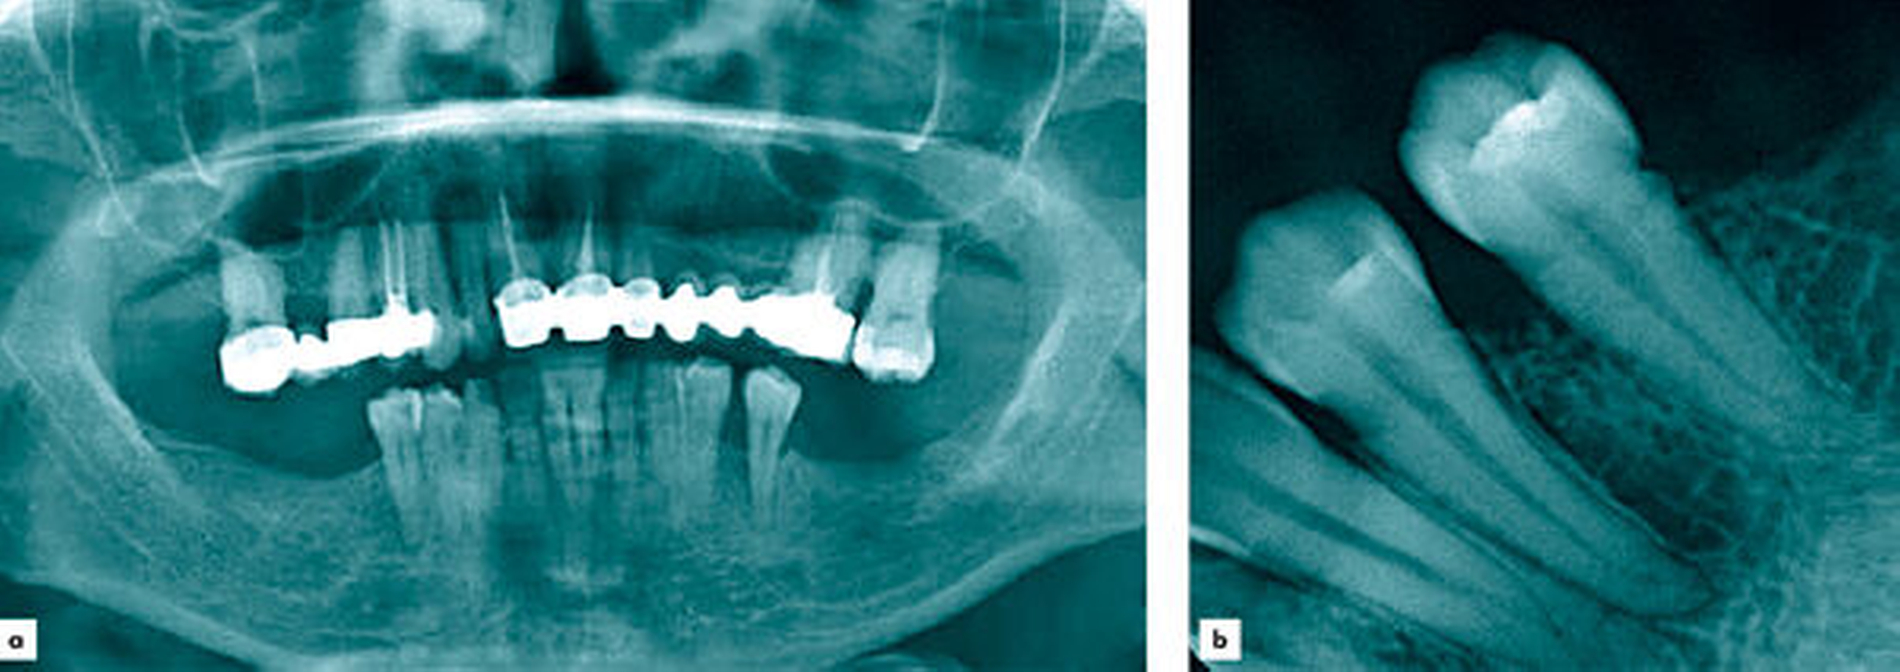

Bei der klinischen Untersuchung zeigte sich eine circa 1 cm messende kugelige Gingivaproliferation regio 34/35 (Abbildung 1). Anamnestisch ergaben sich ein Nikotinkonsum von 7 Packyears (aktuell reduziert) sowie nach Auskunft der Patientin leichte, ziehende Schmerzen in der entsprechenden Region. Die Patientin befand sich zum Zeitpunkt der Vorstellung in der siebten Schwangerschaftswoche. In der Panoramaschichtaufnahme sowie in der Einzelzahnaufnahme zeigte sich eine Abnahme der krestalen Knochenhöhe im Bereich der bereits gelockerten Zähne 34 und 35 (Abbildung 2). Zum Ausschluss eines Malignoms erfolgte noch am selben Tag eine Biopsieentnahme. In der kritischen Wertung der Histologie heißt es: „Akanthotisch verbreitertes Plattenepithel mit unterlagernder Fibrose und teils myxoider Transformation. Einer solchen Verbreiterung des Stratum spinosum kann eine mechanische Irritation zugrunde liegen. Das Resektat weist in diesem Fall eine Unterbrechung des Plattenepithels in ein langstreckiges Ulcus mit gemischtzelligem Entzündungsinfiltrat an seinem Grund auf.“